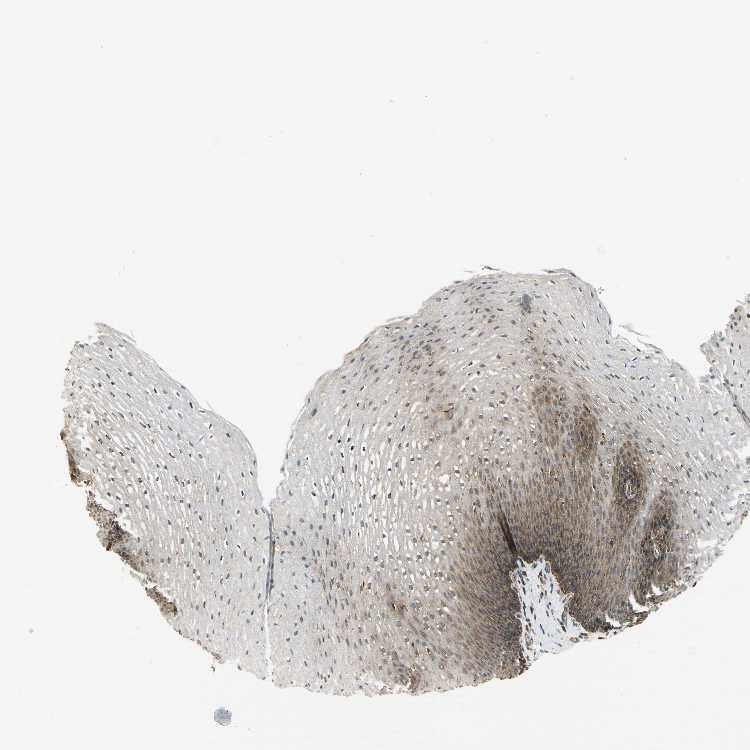

ESOPHAGUS - Antibody stainingi

Antibody staining in the annotated cell types in the current human tissue is reported as not detected, low, medium, or high, based on conventional immunohistochemistry profiling in selected tissues. This score is based on the combination of the staining intensity and fraction of stained cells.

Each image is clickable and will lead to virtual microscopy that enables deeper exploration of all samples and also displays staining intensity scores, fraction scores and subcellular localization as well as patient and tissue information for each sample.

Antibody HPA002997

Squamous epithelial cells Medium